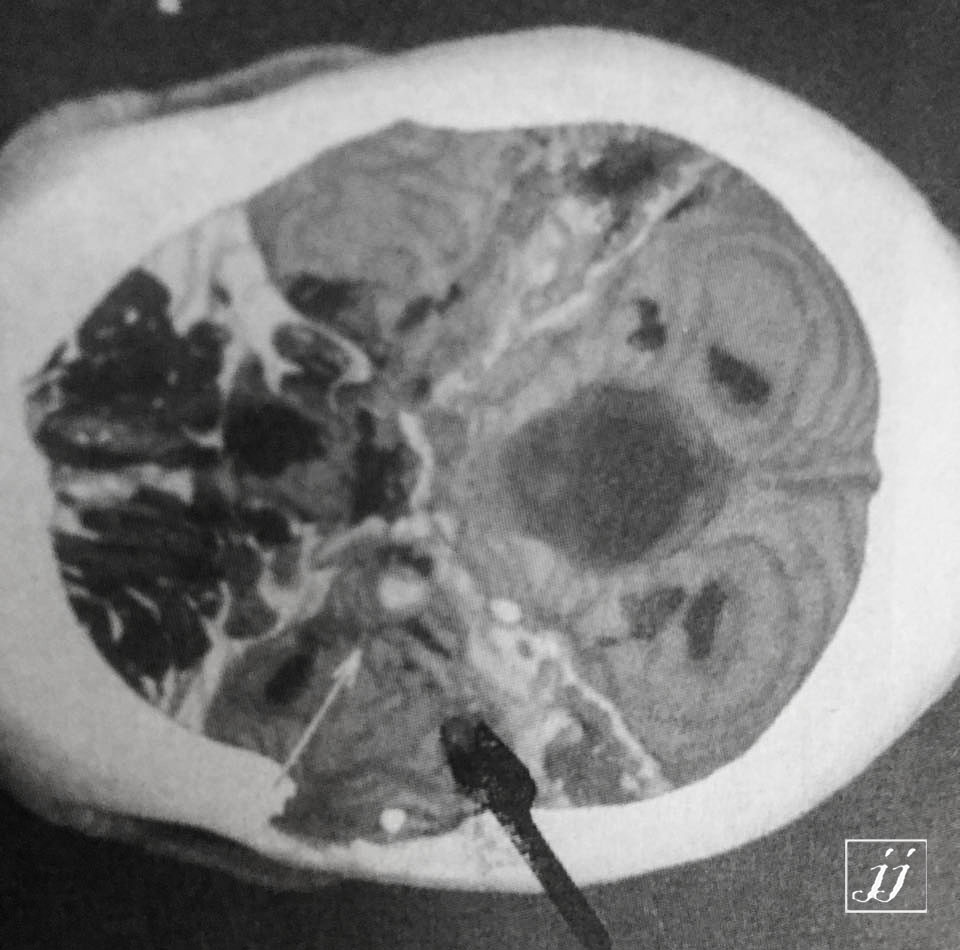

Brain- skull base metallic foreign body (3)